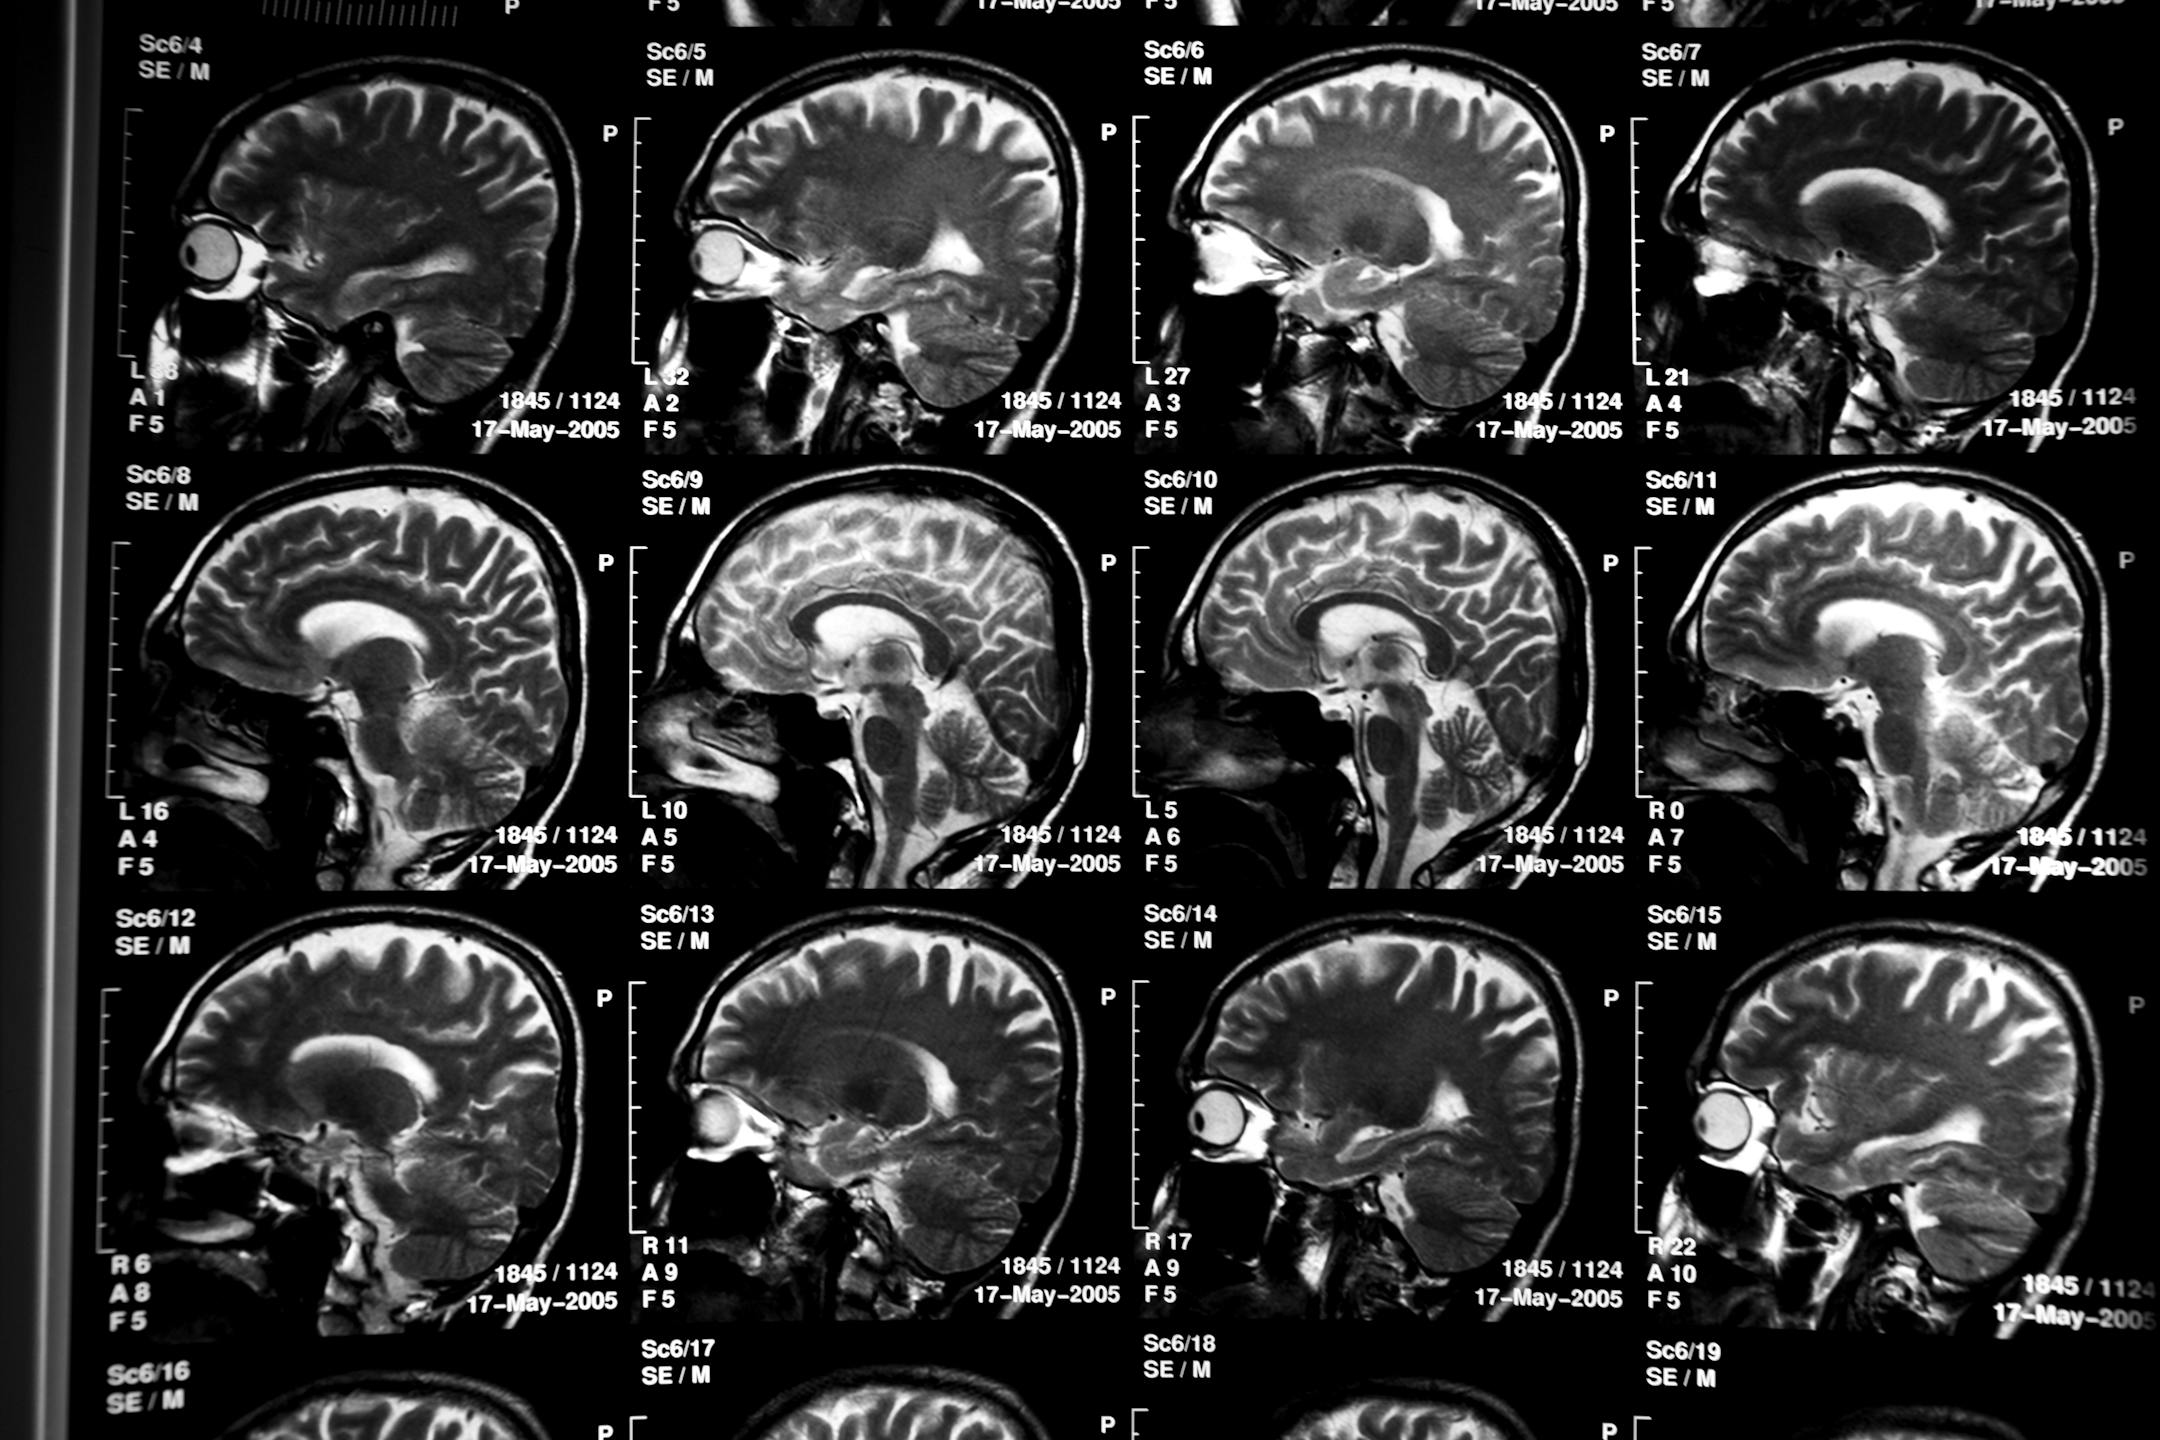

FILE-- Scans of Carlos Cuarta's brain, who suffers from Alzheimer's disease, in Yarumal, Colombia, Feb. 2, 2010. All three of Cuarta's children were afflicted with the disease while in their 40's. Federal officials in the U.S., on May 15, 2012, announced a clinical drug trial, which could lead to treatments for Alzheimer's disease for people who are genetically guaranteed to suffer from the disease but do not yet have any symptoms. (Todd Heisler/The New York Times)

Scans of Carlos Cuarta's brain, who suffers from Alzheimer's disease, in Yarumal, Colombia, in 2010. (Todd Heisler/The New York Times)